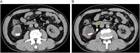

1. 片側の腰背部痛や側腹部痛では水腎症を念頭に置き、まず超音波検査を行い、尿路閉塞の位置と原因を同定するには単純CTを撮影する。